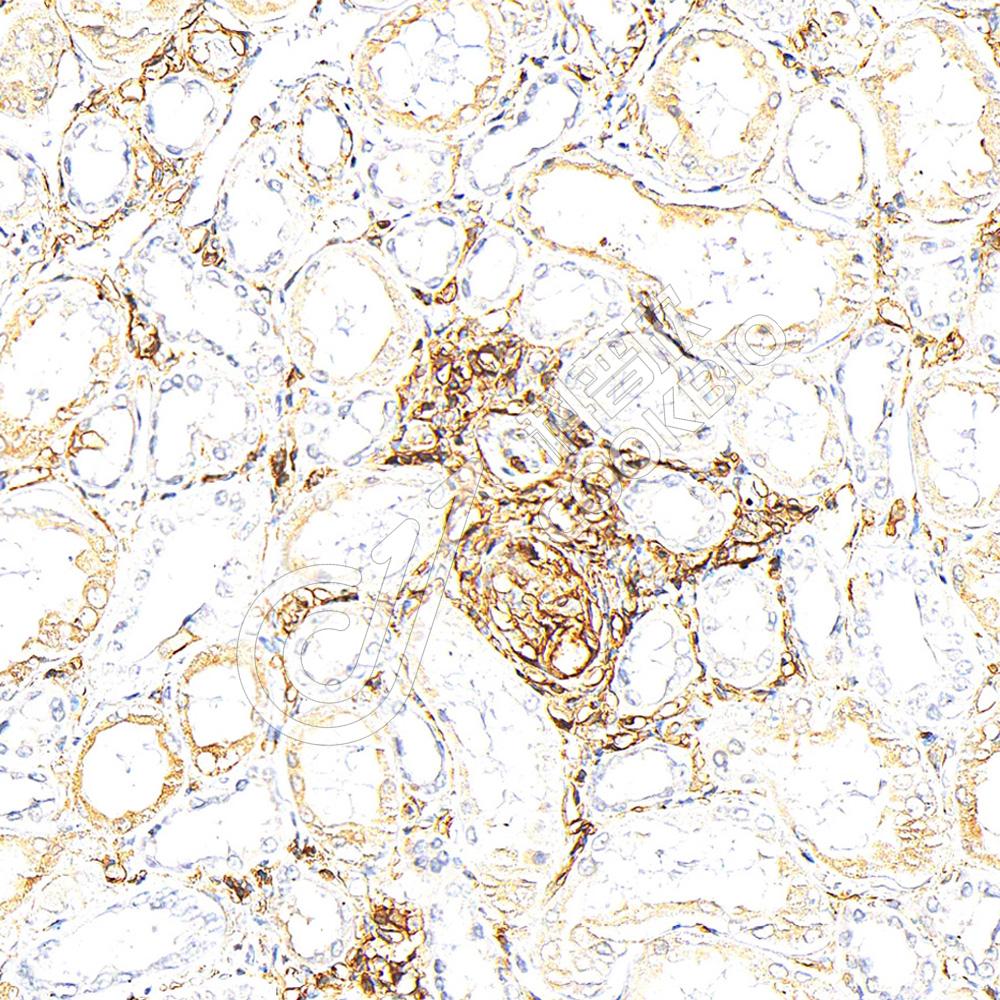

IHC检测CD44蛋白(货号 K5456162).

样品: 人肾, 4%多聚甲醛 (货号KSG1101) 固定12-24小时.

抗原修复: 柠檬酸抗原修复液(干粉, pH 6.0) (KSG1201), 高压锅均匀喷气计时2分钟.

—抗: 1: 800稀释, 4℃ 孵育过夜.

二抗: S-vision免疫组化多聚二抗(山羊抗小鼠), 即用型(货号KB3903), 室温孵育20分钟.